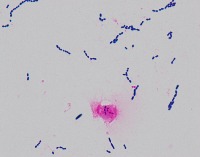

Medical Research: This model can be utilized in the field of medical microbiology and research to classify bacterial strains based on their visual characteristics in lab experiments and for the study of bacterial growth processes.

Healthcare Diagnostics: In healthcare, the "assembly" model could be used to assist in bacterial diagnosis in clinical lab settings, identifying the presence of specific forms of bacteria like Staphylococcus, Streptococcus, B-catarrhalis, Str_pne, and Enterococcus in samples.